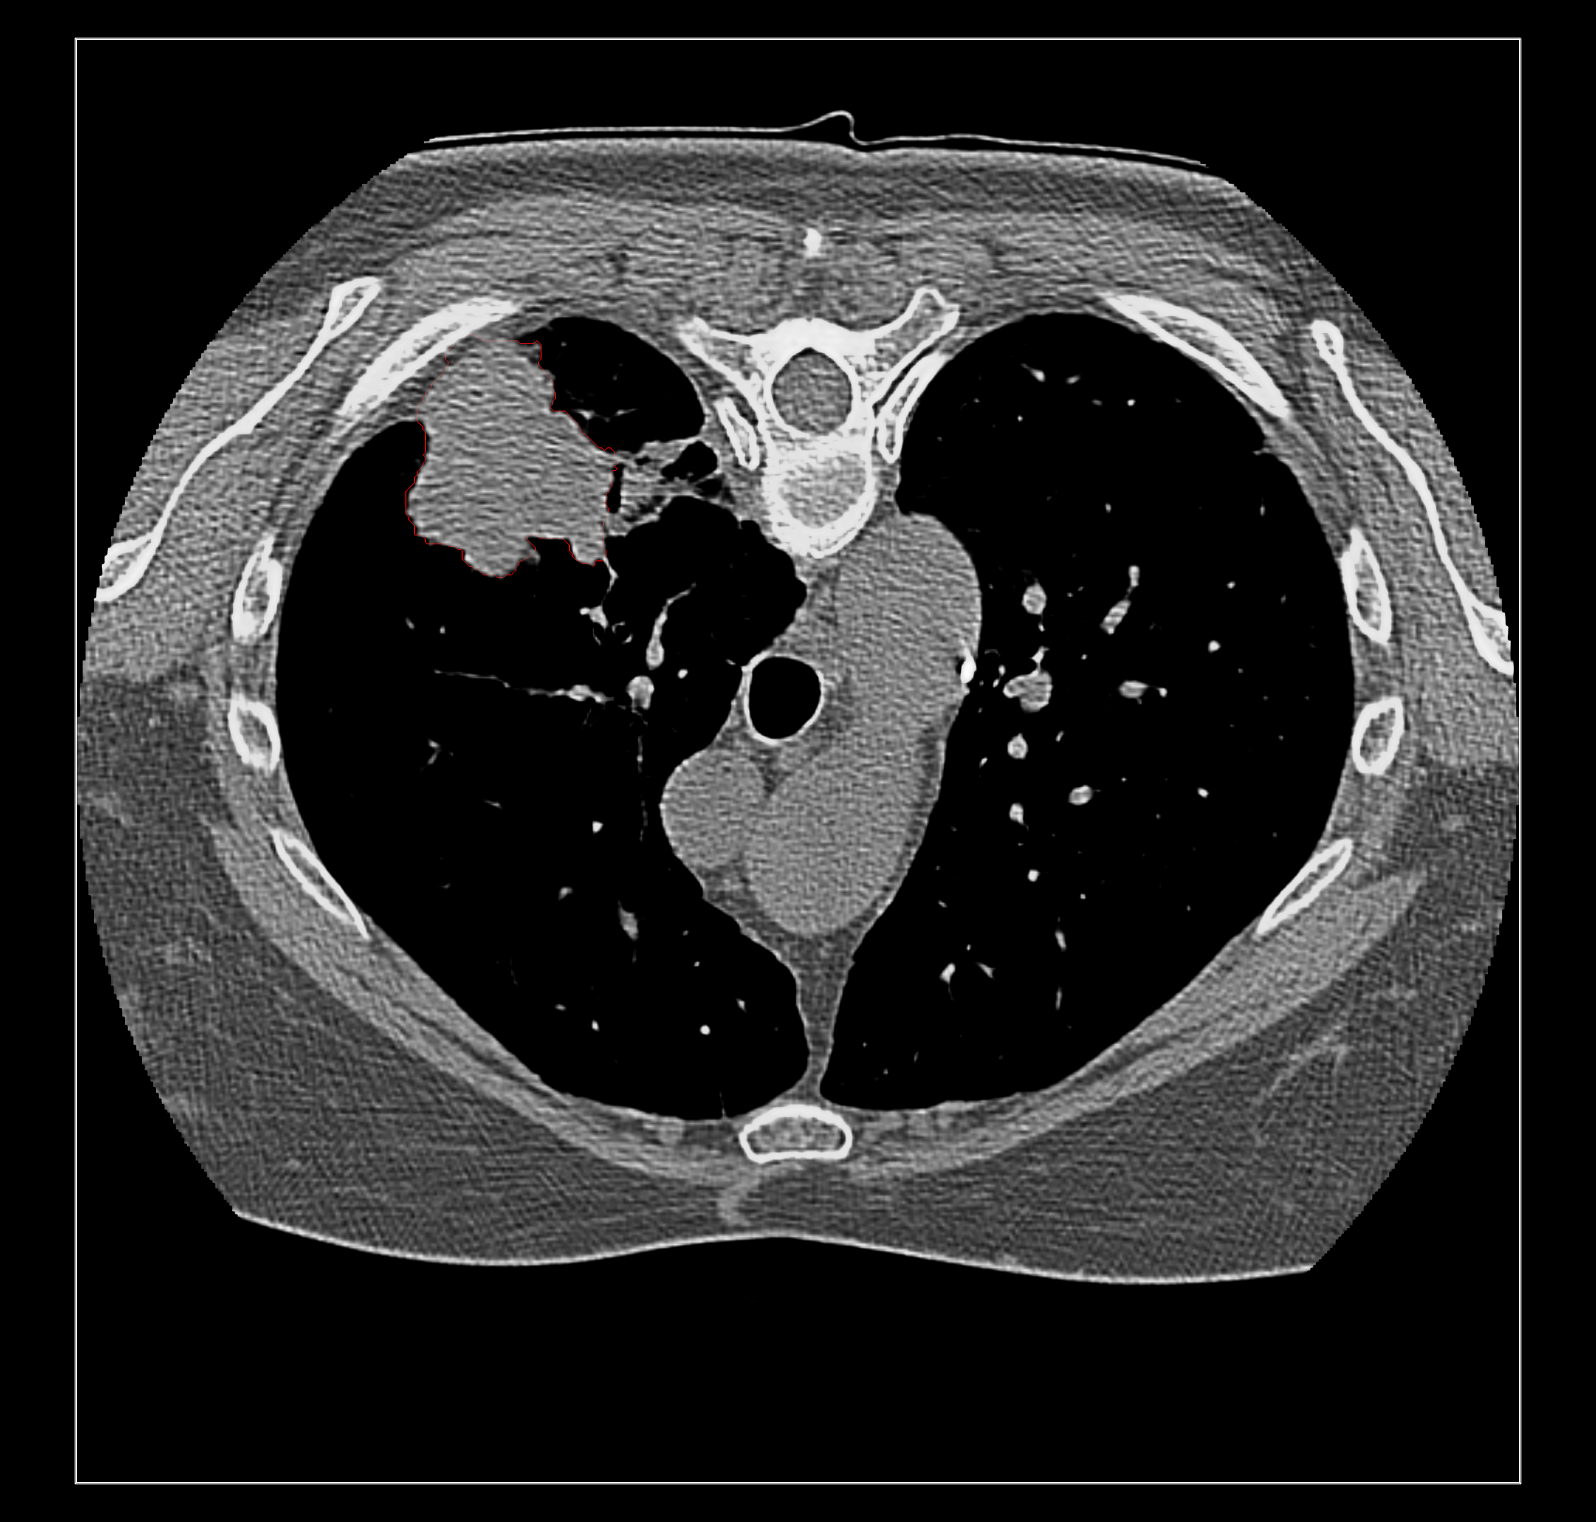

Surface rendering of a segmentation with image rendering of a CT scan can look ok, and only the outline of the surface can be shown using volume command "capFaces false". Showing both segmentation and CT as image also works fine if the brightness curve is not narrow. I've attached images for all 3 styles made with

open /Users/goddard/ucsf/data/dicom/11-06-2014-1-96508-subset format dicom

volume #1.1.1.1.2 style surface

volume #1.1.1.1.2 style surface capFaces false

}}}

The capped surface flickers badly when rotating because the surface cap is at exactly the same depth as the image plane so a rendering depth fight ensues.

The surface style with plane CT image display adjusts when the plane is moved with the slider since the CT and segmentations are grouped as multichannel volume data.